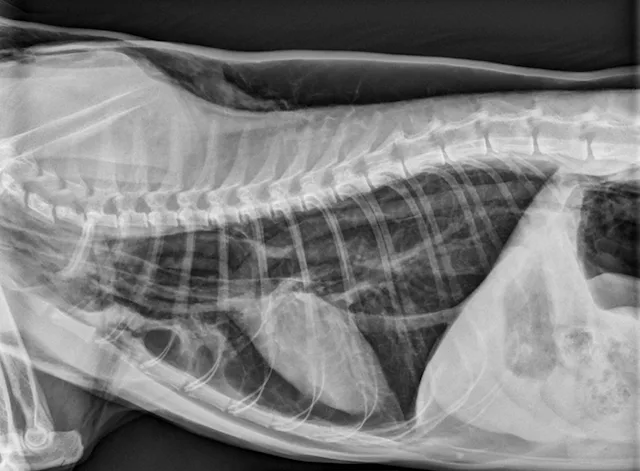

Radiography can be used to diagnose tracheal tears (Figures 1 and 2). If a tracheal tear is present, thoracic radiographs may reveal pneumomediastinum, subcutaneous emphysema, pneumoretroperitoneum, hyperinflated lung fields, a gas-filled pseudo-airway at the level of the rupture, focal narrowing of the tracheal lumen, and/or pneumothorax if the mediastinum has been perforated due to air pressure.3